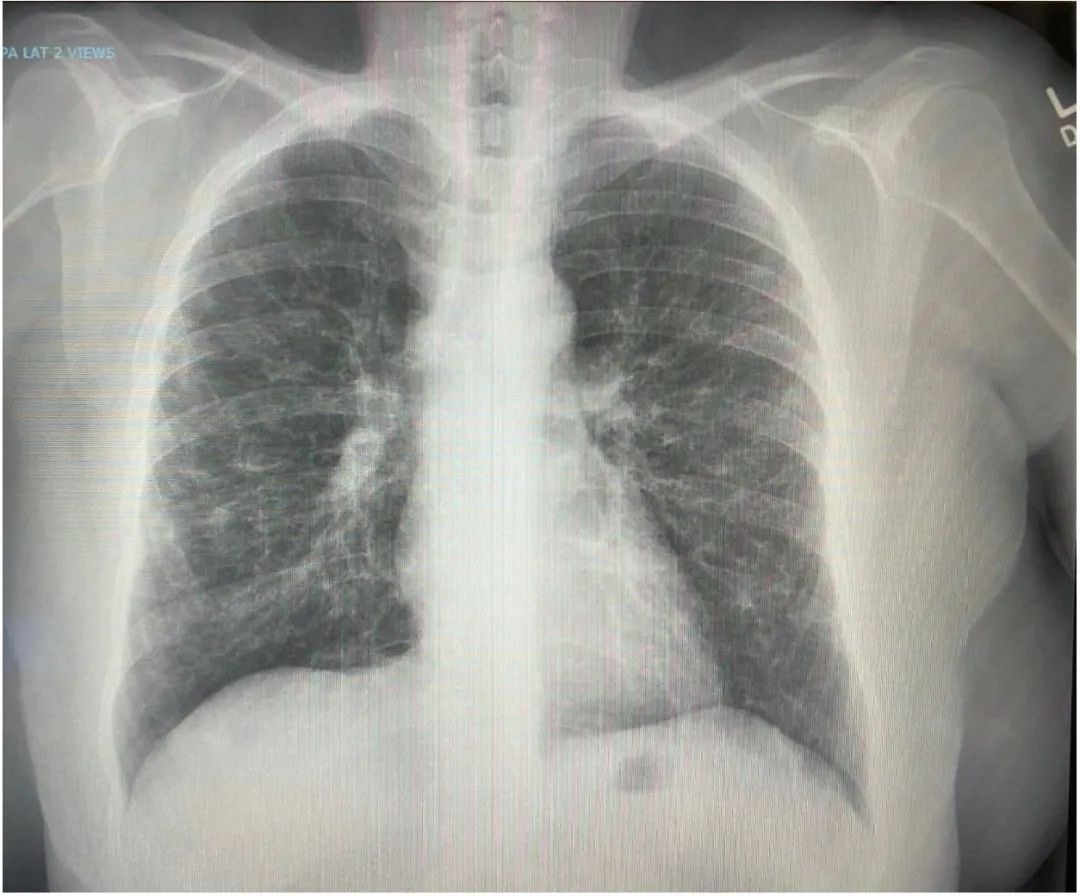

由于病情恶化过快,普通医院已无法处理,患者被转院至代表美国最高医疗水平的西达塞纳医学中心进行进一步治疗。转院后,医护人员检测了患者的各项体征指标,数据显示,患者体内出现了绝对性淋巴细胞减少(490cells/μL),多项炎症相关指标提升幅度惊人。(C反应蛋白:217mg/L、Il-6:56 pg/mL、TNF-alpha:7.4ng/mL)。胸腔X光显示出极严重的双侧肺浸润。

患者肺部出现严重的双侧肺浸润(左),右图为正常肺部X光,供参考